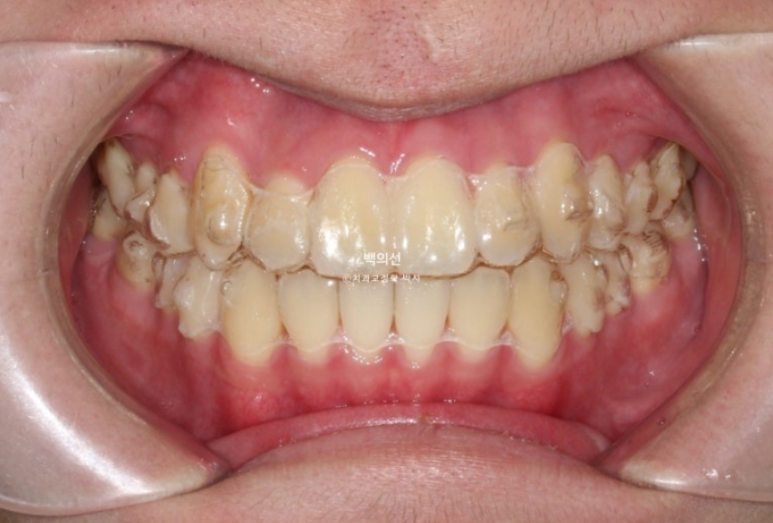

24년 2월, 교정치료를 위해 온 환자분입니다.

24.04

송곳니 덧니가 있고 덧니 옆 앞니는 입천장으로 나서 아랫니가 거꾸로 물리는 반대교합 입니다.

교합이 뜨는 부분들이 있습니다.

어금니 교합은 좋고 돌출이 없어서 치간삭제 소량 동반한 인비절라인 라이트 권유드렸습니다.